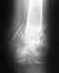

Вы так и не указали дату операции. Предполагаю, что прошло больше 2 мес.

На снимках все хорошо.

Нагрузка возможна та, которая получается без хромоты. Т.е. если можете идти, не хромая, без костылей и трости - на здоровье. Если сильно хромаете - пользуйтесь дополнительной опорой в противоположной руке. Движения в колене надо уже разработать, уже должны свободно садиться на корточки.